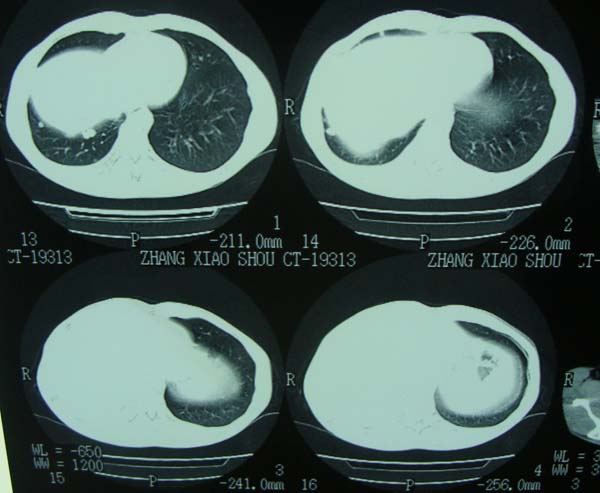

标题: CT15132:男,26岁。建筑混凝土工人。发热。咳。 [打印本页]

标题: CT15132:男,26岁。建筑混凝土工人。发热。咳。

右肺继发型肺结核,右侧胸腔积液、胸膜肥厚粘连。

右肺及胸胸膜多个结节多考虑转移瘤,右侧胸水,结核次之。

右肺继发型肺结核,右侧少量胸腔积液、胸膜肥厚。

右肺继发型肺结核,右侧胸腔积液。